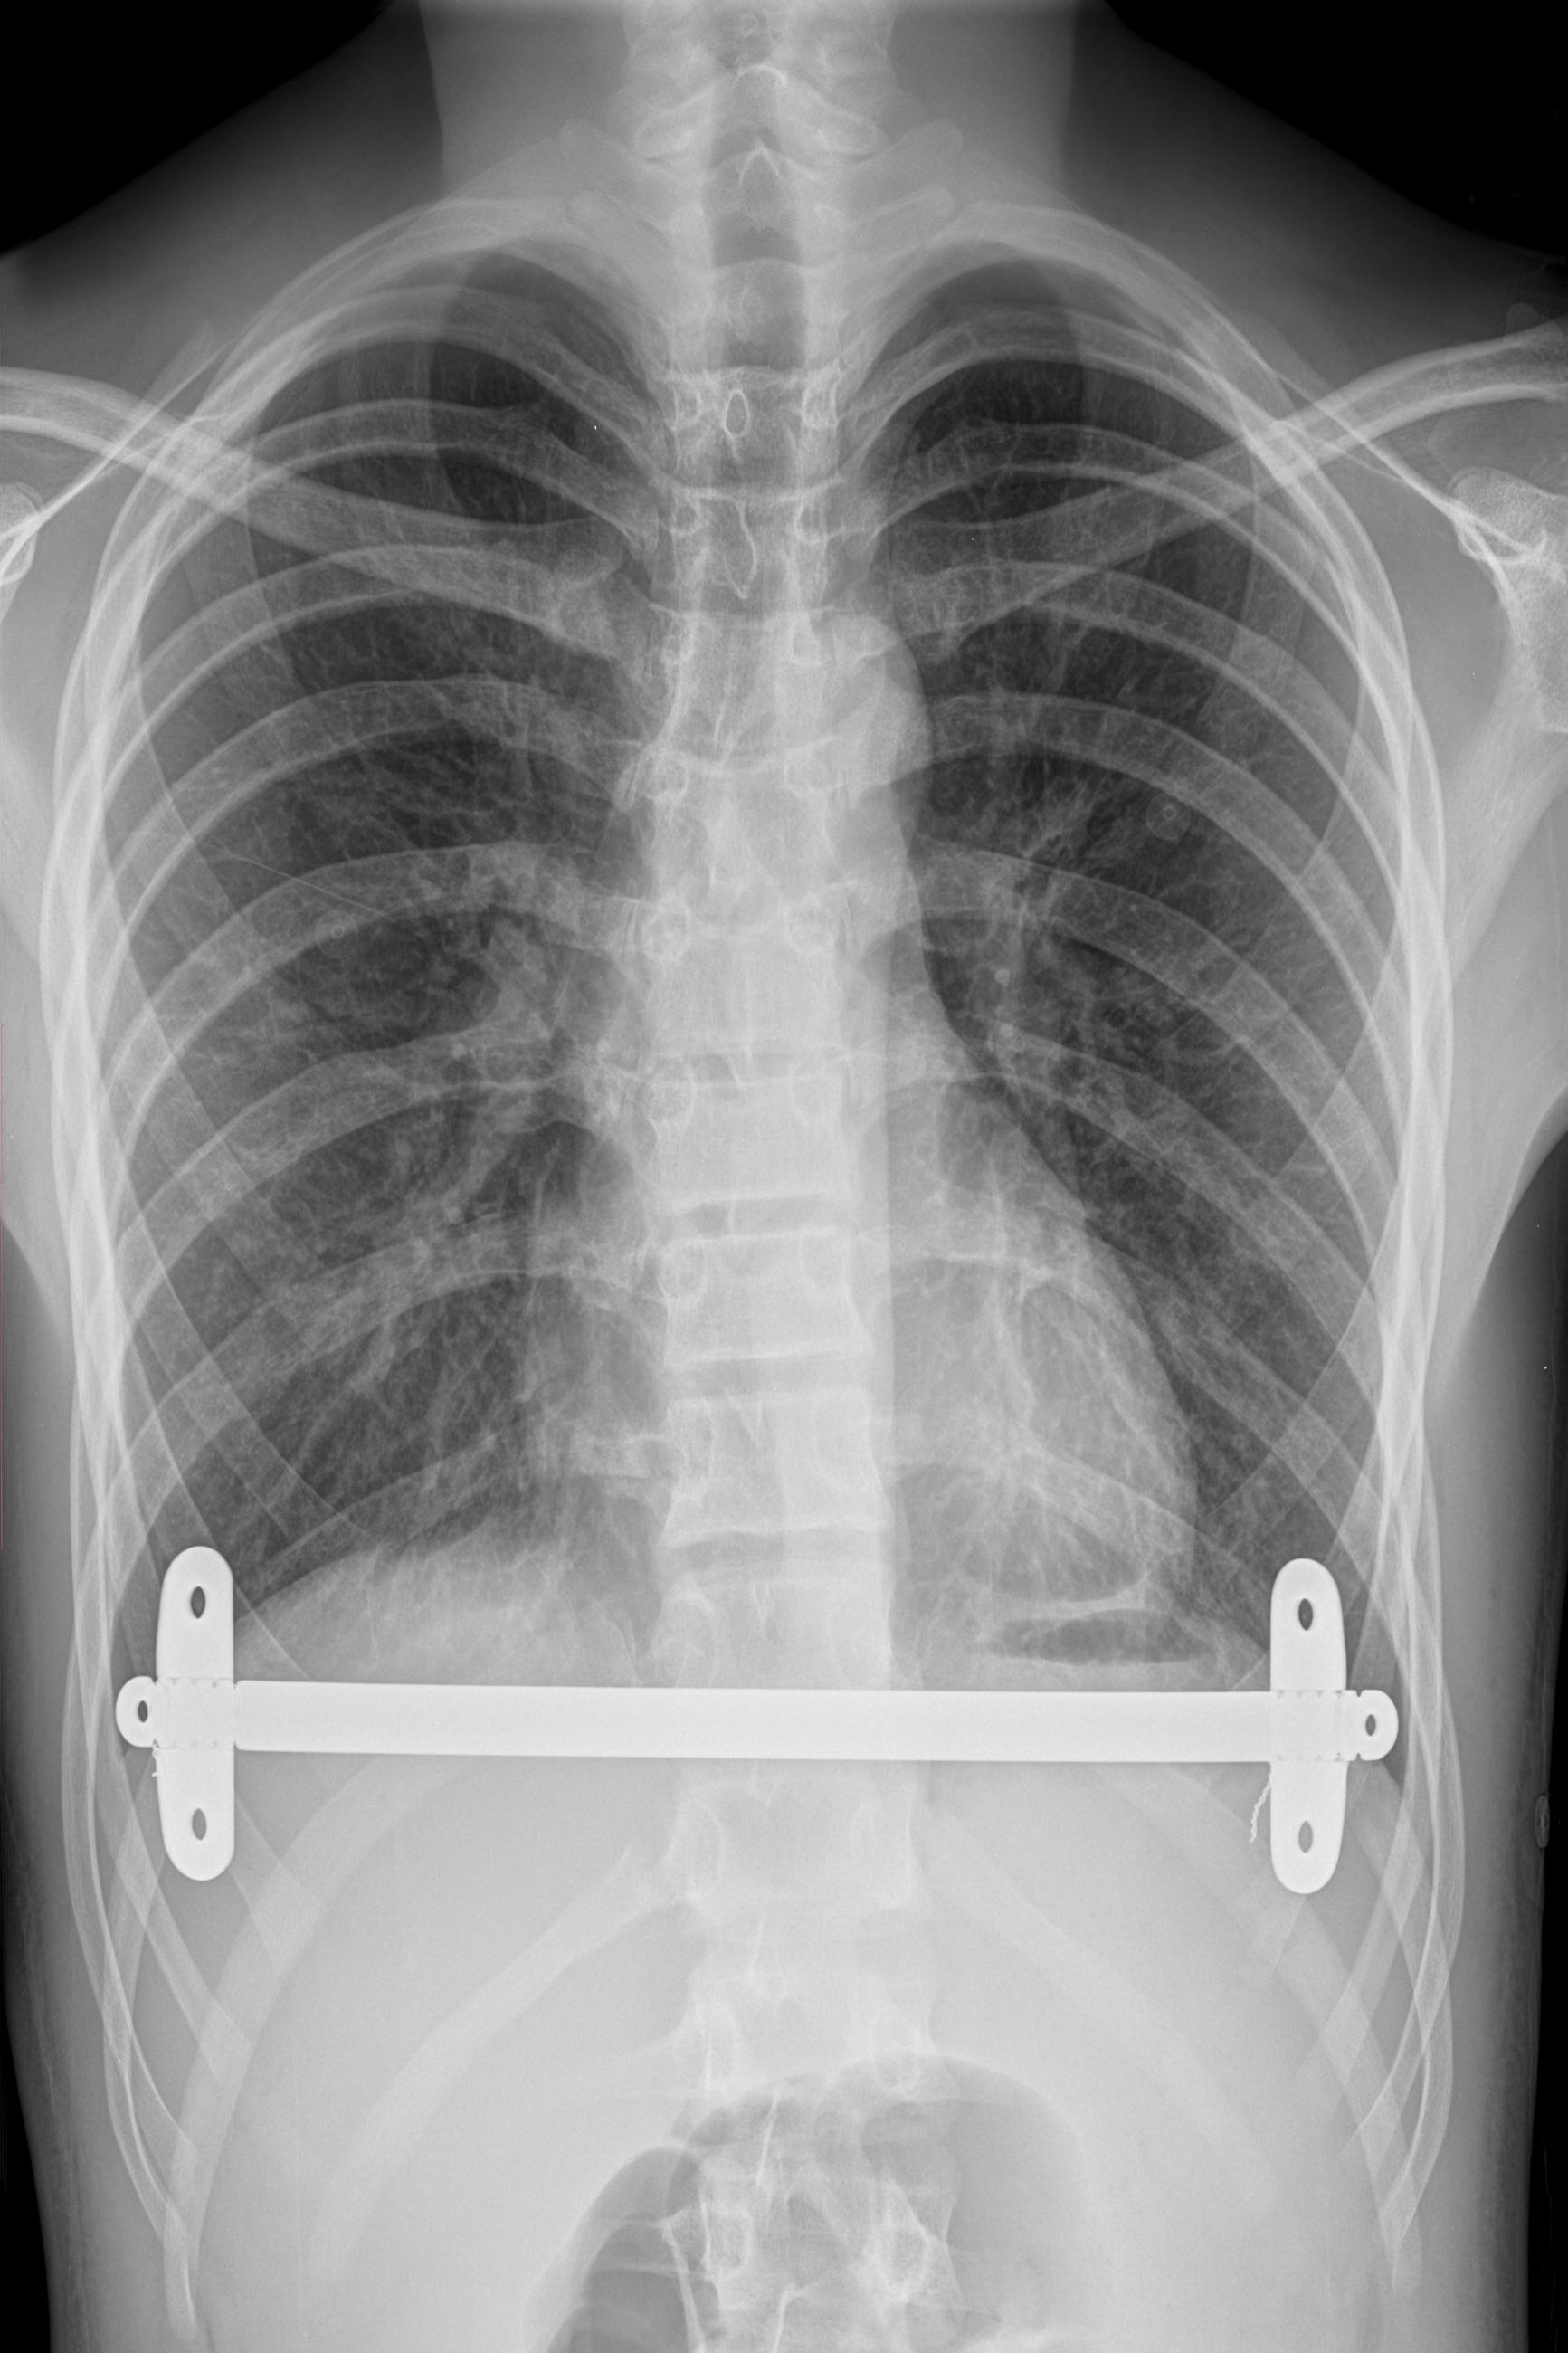

X-ray

An X-ray of the steel bar inside my body, under my rib cage and over my heart and lungs. The image was modified slightly to remove some text over the image and to show more of the human form. This image and the photograph of the front of my chest form a diptych, with each image echoing the other.